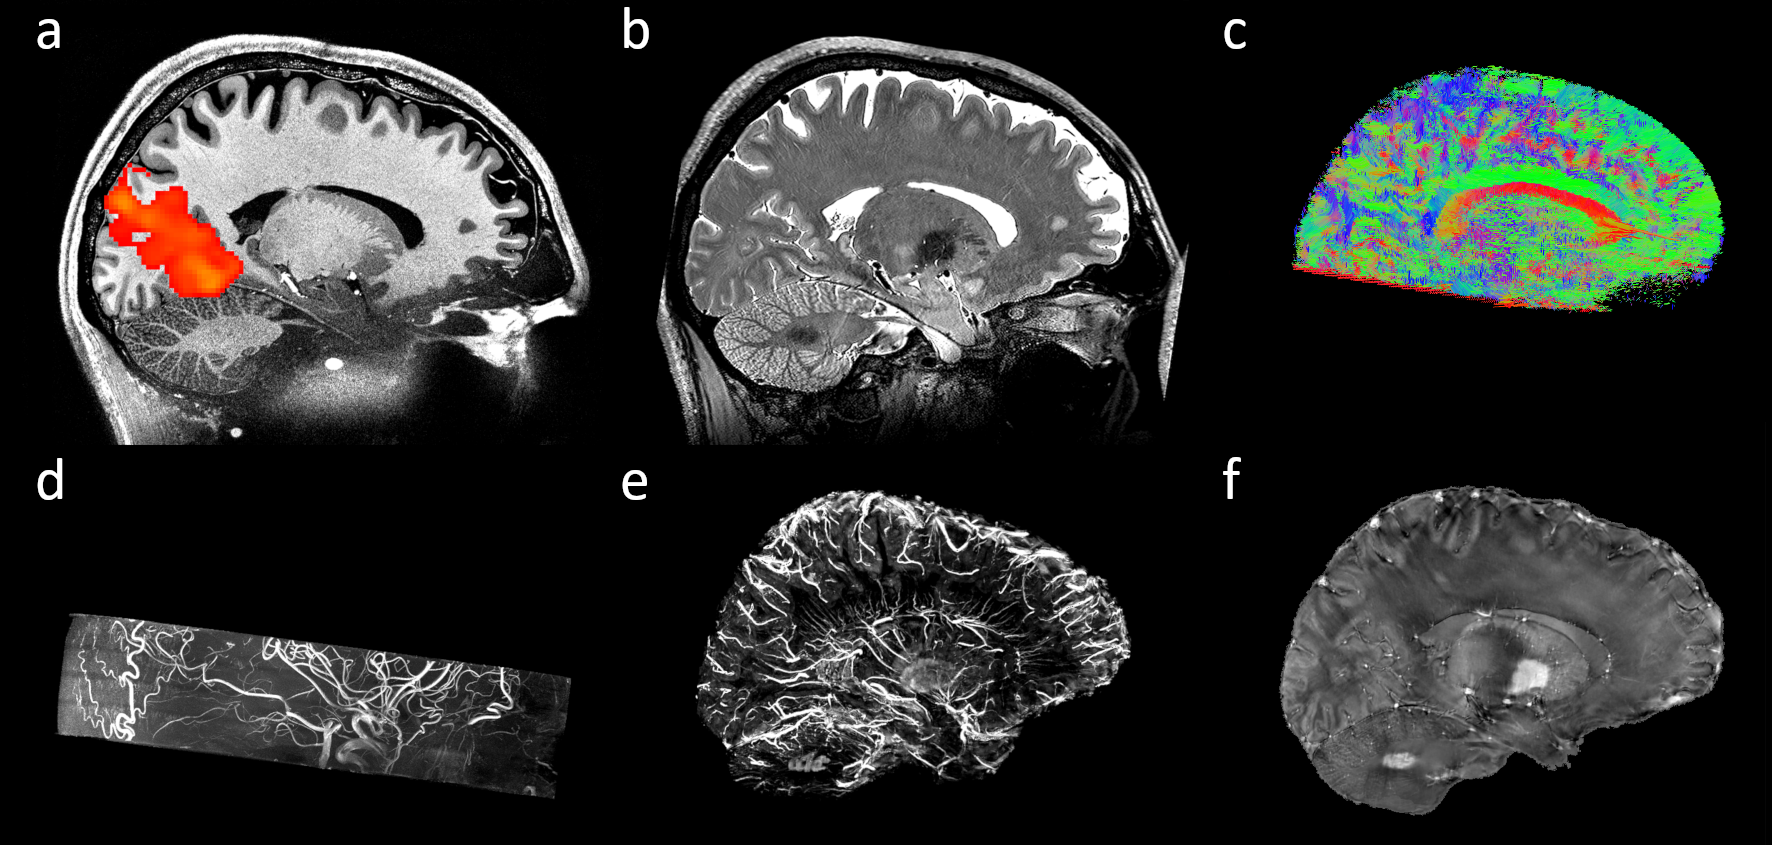

Today, we are happy to share a decade worth of MRI data of a single participant as a human phantom in our recent data descriptor published in Scientific Data available here: https://rdcu.be/clgFK. We present an extension to our previous dataset containing multiple additional contrasts with ultrahigh isotropic spatial resolution and (mostly) full brain coverage. In total, 202 volumes were acquired across 66 scanning sessions using an ultrahigh field 7 Tesla MR scanner (Siemens Heathineers, Erlangen, Germany). This includes up to 150 μm time of flight (ToF) angiography, 250 μm MPRAGE, 330 μm quantitative susceptibility mapping (QSM), up to 450 μm T2-weighted turbo spin echo (TSE), eight 700 μm T1-weighted back-to-back scans with low and high signal to noise ratio (SNR), 800 μm diffusion tensor imaging (DTI), one hour continuous 1.8 mm resting-state functional MRI (rs-fMRI), and more than 120 other MPRAGE volumes collected over 10 years with varying isotropic spatial resolution between 450 μm and 1 mm as well as many corresponding proton density weighted volumes with the same spatial resolution as the MPRAGE volumes.

Therefore, we expect this new dataset to be used in many multimodal processing schemes, e.g. data fusion for visualization as well as teaching, building of brain atlases, vascularization of subcortical structures such as the hippocampus, validation of connectivity models based on joint DTI and rs-fMRI data and many things beyond. Due to its ultrahigh resolution and high quality, we expect to see structures that were never identified before in vivo. Further, structural and vascular differences in the laminar organization of the cortex could be investigated by assessing jointly the MPRAGE (cortical delineation), QSM (iron, myelin proxy; venous vasculature), ToF (arterial vasculature), and DTI (intra-cortical fiber tracts). The MPRAGE volumes have been collected over ten years and can be used in different kinds of studies. First and foremost, they can be used to conduct longitudinal studies. This could for example indicate longitudinal changes across time. However, since the scanning protocol is not identical for every measurement, this could be an ideal test bed for novel data harmonization algorithms to avoid potential bias in data assessment. Furthermore, data is included in back to back studies within the very same session and with artificially reduced SNR. This may allow for test-retest studies in software development and to validate denoising algorithms as ground truth data can be generated. Beyond that, the scanner's rawdata of the back to back scans are available which allow for development and benchmarking of advanced reconstruction algorithms.